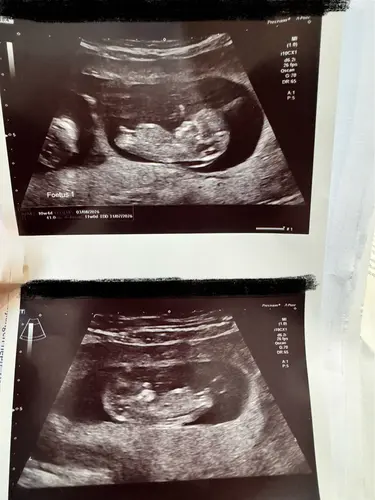

Paar dagen vooruit gezet, wordt 1-8. Allebei helemaal in orde en lekker druk 🥰